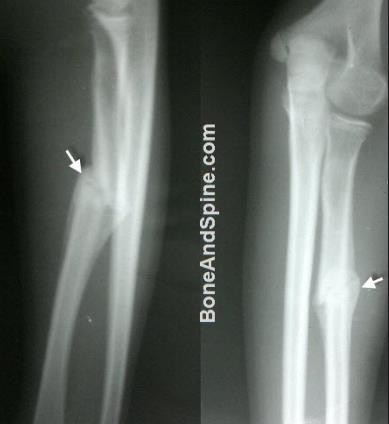

- X quang:

- Cho phép chẩn đoán xác định gãy xương

- Xác định kiểu gãy: đơn giản (gãy ngang, gãy chéo xoắn…), phức tạp (gãy nhiều tầng, nhiều mảnh…), xuyên khớp.

Hình : Các loại gãy xương thường gặp

(ngang, xoắn, chéo, nhiều mảnh, rời)

- Xác định di lệch. có 4 loại di lệch thường gặp:

- Di lệch chồng gây ngắn chi

- Di lệch sang bên làm chi sưng nề.

- Di lệch gấp góc và di lệch xoay làm lệch trục chi.